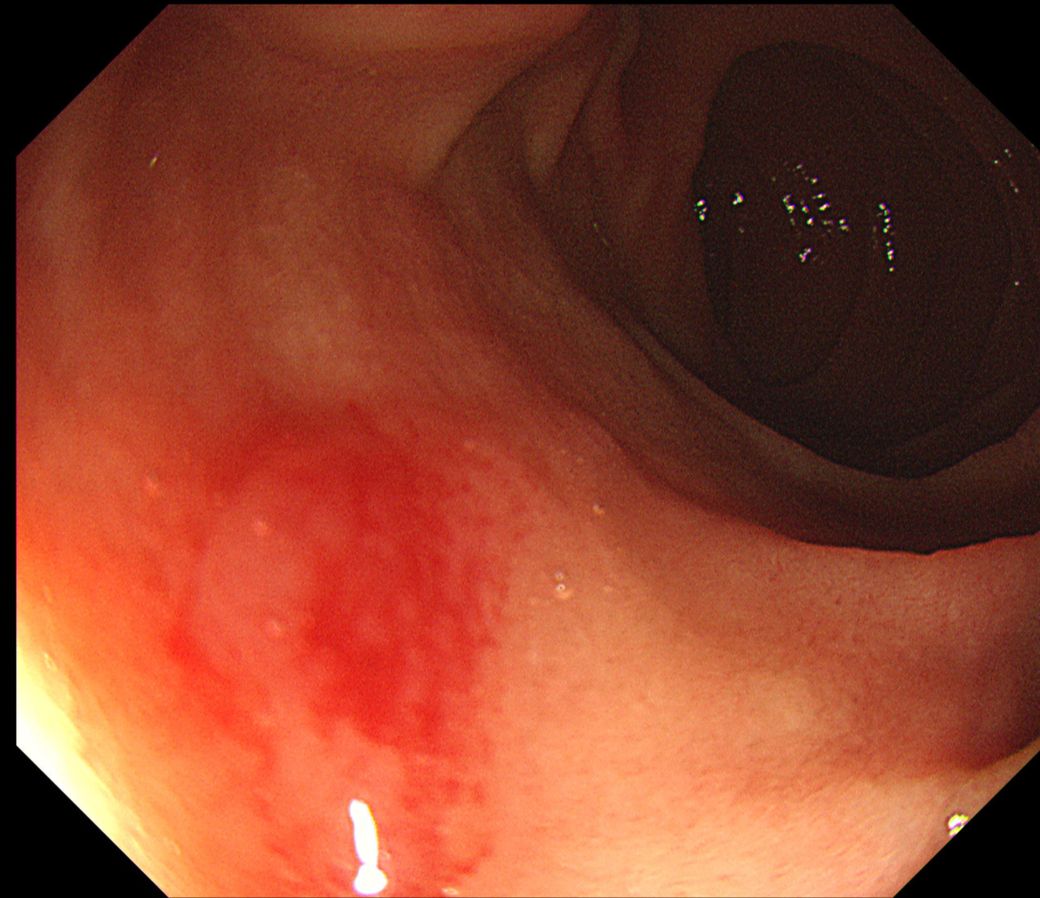

아래 사진이 바터팽대부가 맞나요? 바터팽대부는 정상인가요?

• 2번 째 사진

박터팽대부는 크게 이상이 있는 소견으로 판단되지는 않습니다. 바터팽대부는 실제로 돌출이 되어있기에 용종등과 육안상으로 명확히 감별이 안될수 있어 의심이 된다면 조직검사를 하거나 단기간 추적검사를 하는 것을 권장드립니다.